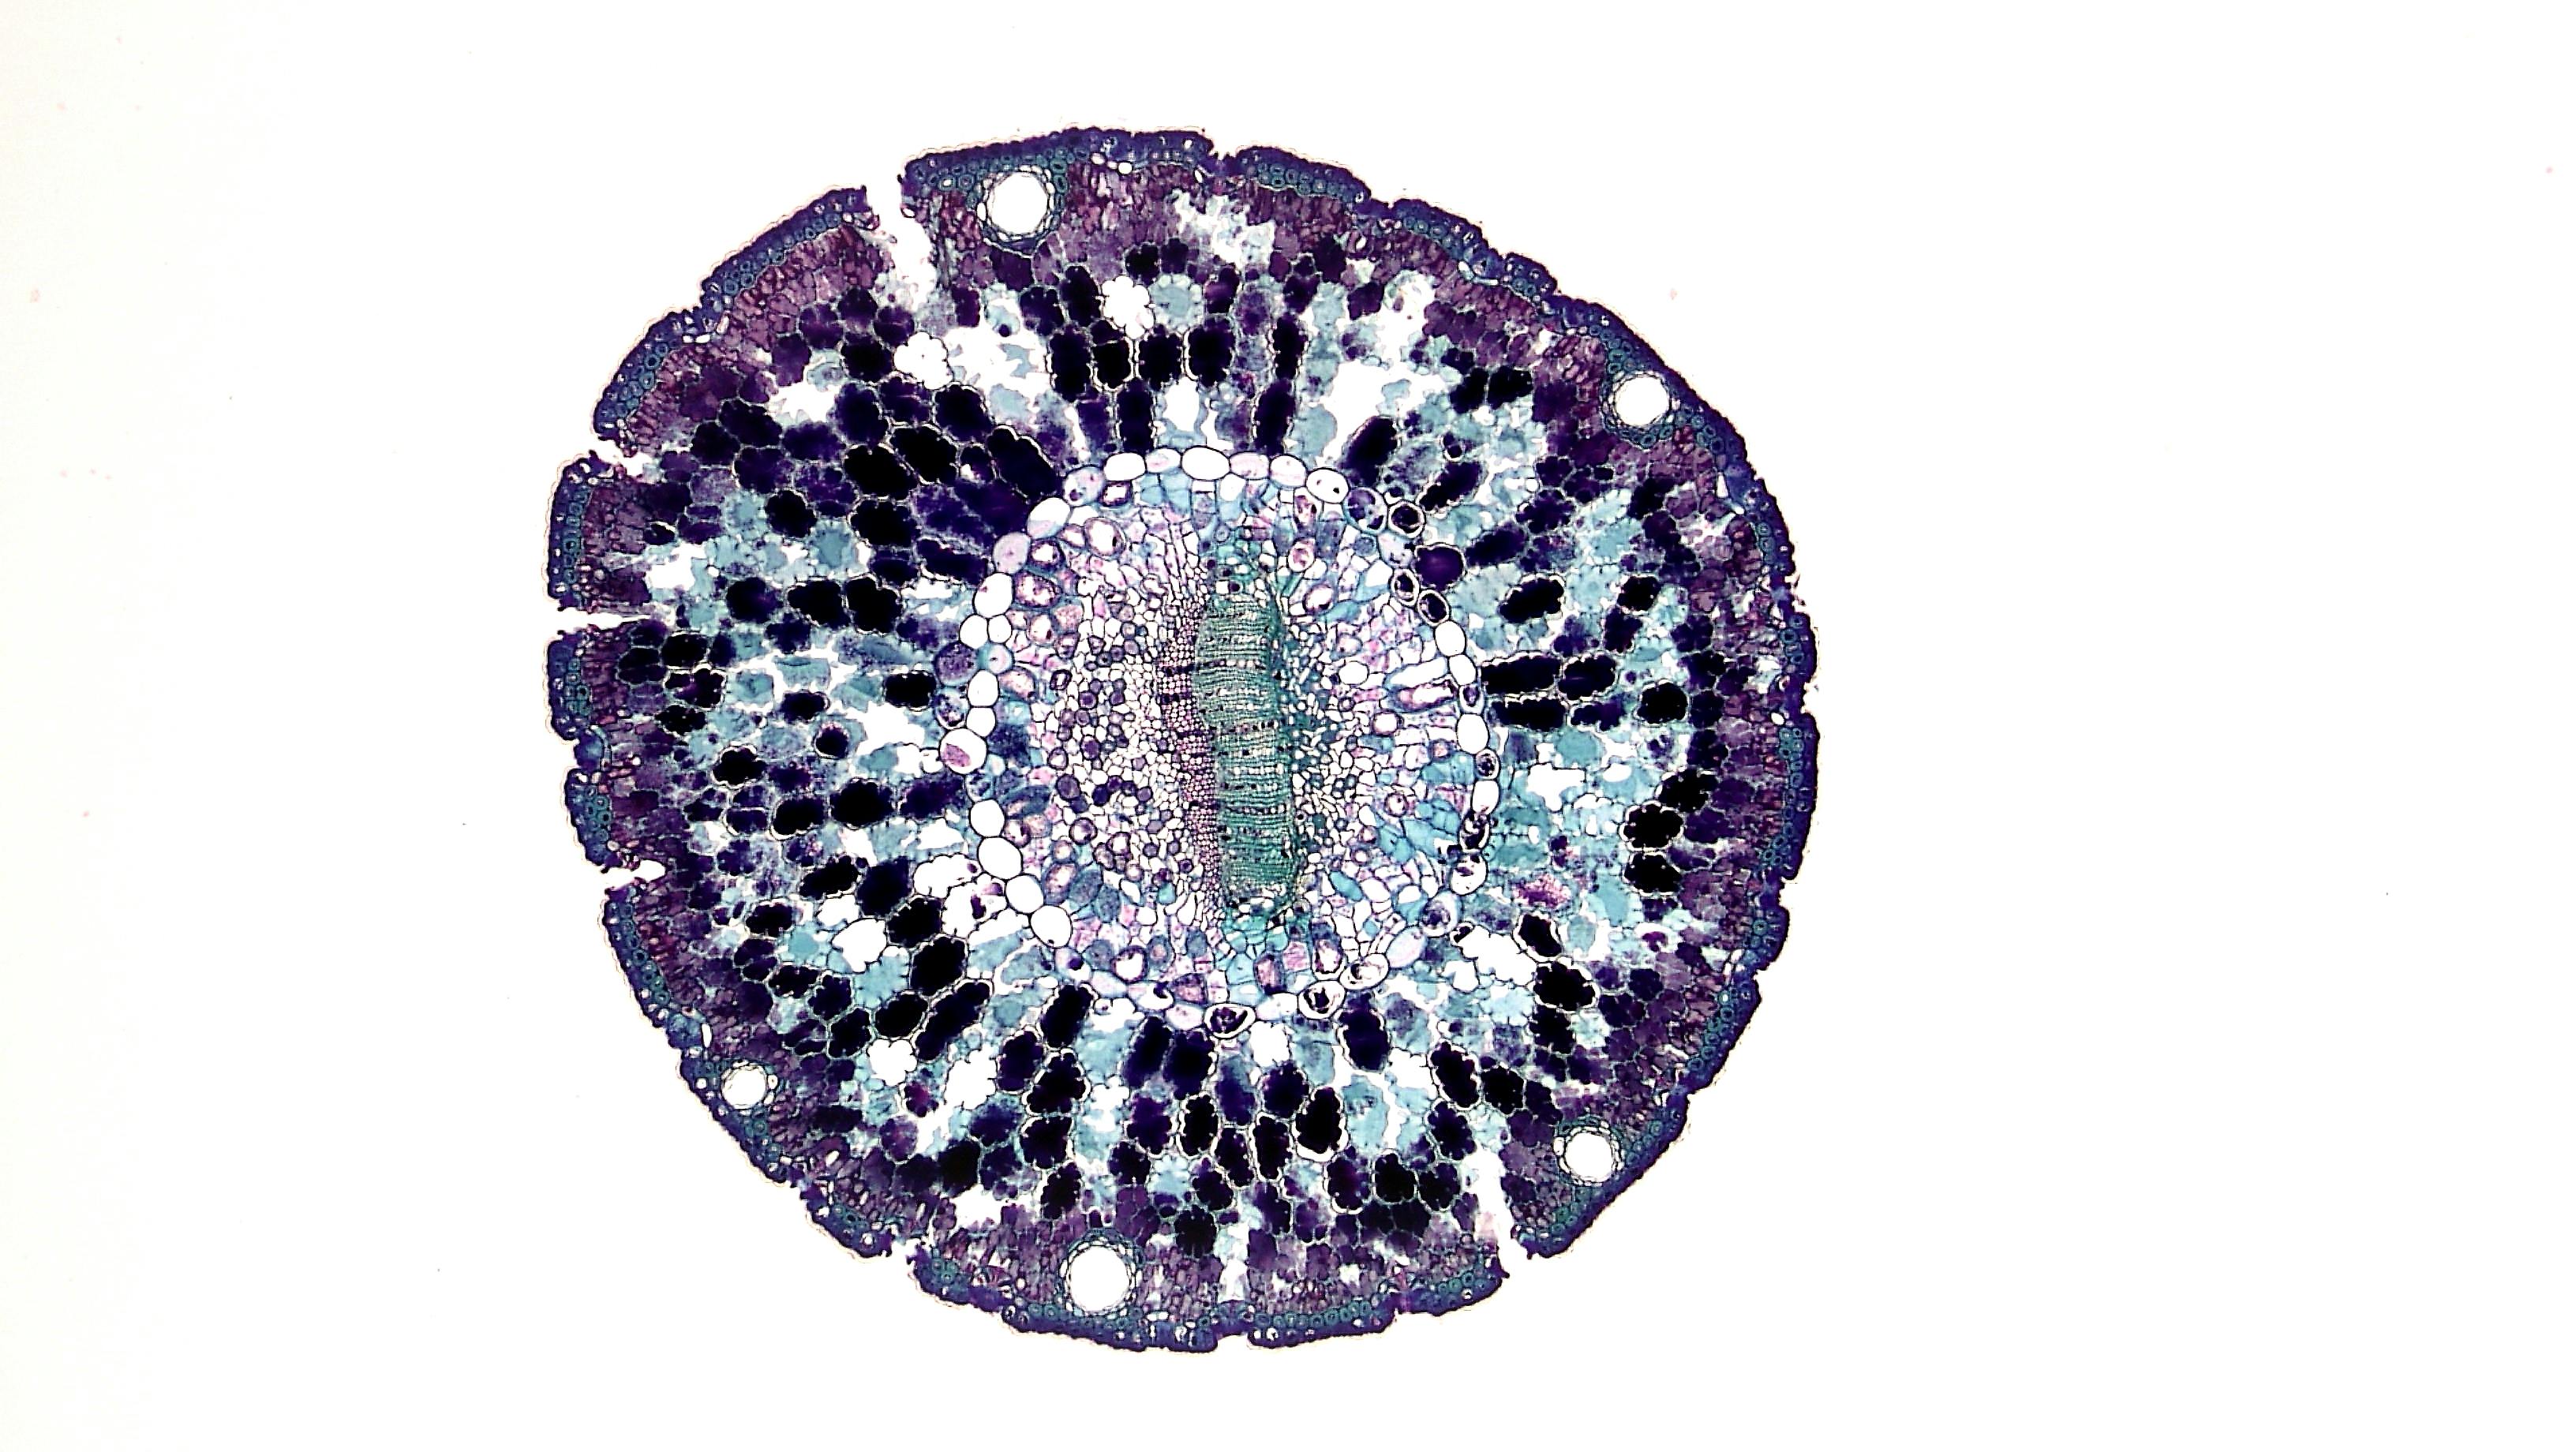

이 칩은 1,000개 이상의 암세포 덩어리를 혈관 세포와 함께 배양하며, 연구자가 원하는 시점에 특정 암세포를 선택적으로 회수할 수 있어 암세포가 치료제에 내성을 가지는 과정을 세밀하게 추적할 수 있습니다.

연구진은 오드세이 칩을 활용하여 유방암 치료제인 타목시펜에 대한 내성 형성 과정을 분석했습니다.

이를 통해 암세포가 어떻게 내성을 획득하는지, 그리고 이 과정에서 어떤 생물학적 원리가 작용하는지를 밝혀냈습니다.

특히, 암세포와 주변 혈관 세포 간의 복잡한 상호작용이 내성 획득에 중요한 역할을 한다는 사실이 드러났습니다.